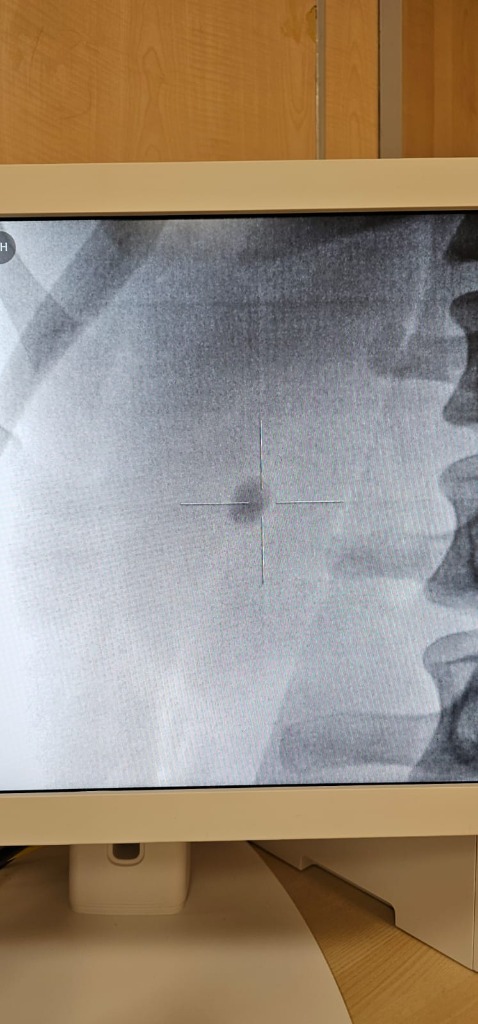

ESWL process under ultrasound control

Before

After

Before ESWL X-ray

After ESWL X-ray